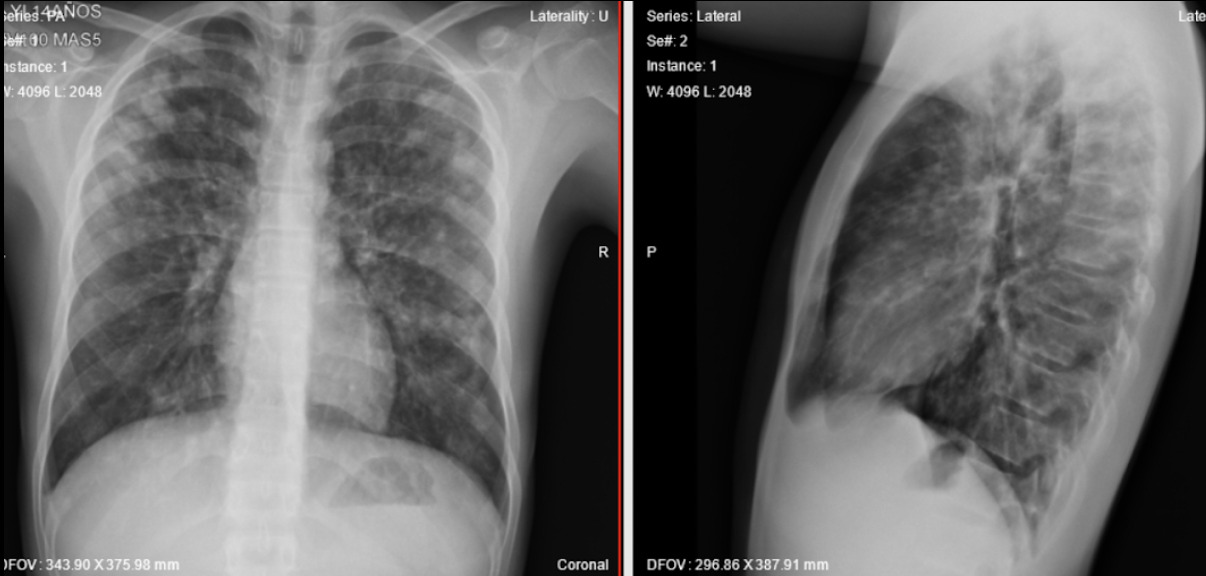

Antecedentes: El edema pulmonar de las alturas se caracteriza por la aparición de edema pulmonar en individuos sanos que se desplazan a lugares por encima de los 2 500 metros sobre el nivel del mar. Reporte de caso: se presenta un paciente de trece años que ingresa al servicio de urgencias por cuadro clínico consistente en la aparición súbita de dificultad respiratoria de asociado a un único episodio emético y dolor torácico. Se decidió tomar laboratorios paraclínicos y radiografía de tórax al ingreso donde se encontraron múltiples hallazgos relacionados con el mal de altura y edema pulmonar secundario. Se dio manejo diurético intravenoso y oxígeno suplementario a bajo flujo. Paciente quien presentó resolución de la enfermedad en dos días de tratamiento, evidenciados en control radiográfico y clínico. Conclusiones: Dada la noxa epidemiológica actual de Sars-Cov-2 y el patrón radiográfico que puede confundirse con tipos de neumonías atípicas, es importante reconocer no solamente imagenológicamente sino clínicamente este tipo de pacientes, la importancia de un manejo adecuado de control de líquidos administrados y eliminados y sus posibles complicaciones.